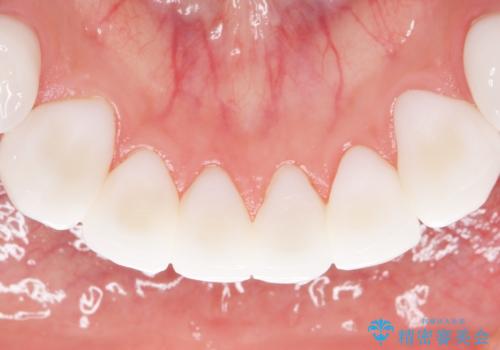

憧れの芸能人のような白い歯に 30代男性

- 憧れの芸能人(ヴィジュアル系バンドマン)のような歯になりたいとのご希望で来院された患者様です。

咬み合わせが悪く矯正も検討されていたそうですが、歯を真っ白にしたいというご希望もあり、28本のすべての歯をセラミックにしたいとのことでした。

精査したところ、ほとんどの歯が保険内のレジンで充填されており、咬み合わせも悪く咬合していない歯もありました。

虫歯をしっかりと治療したのち、オールセラミッククラウンによる補綴治療を行いました。

憧れのヴィジュアル系バンドマンのような白い歯になり、喜んで下さいました。

不適なレジン充填によるデコボコがなくなったことで歯磨きしやすくなり、また気にされていた咬み合わせも良くなり、ご満足頂けました。

クラウンの種類:オールセラミッククラウン スタンダード

シェード:NW0